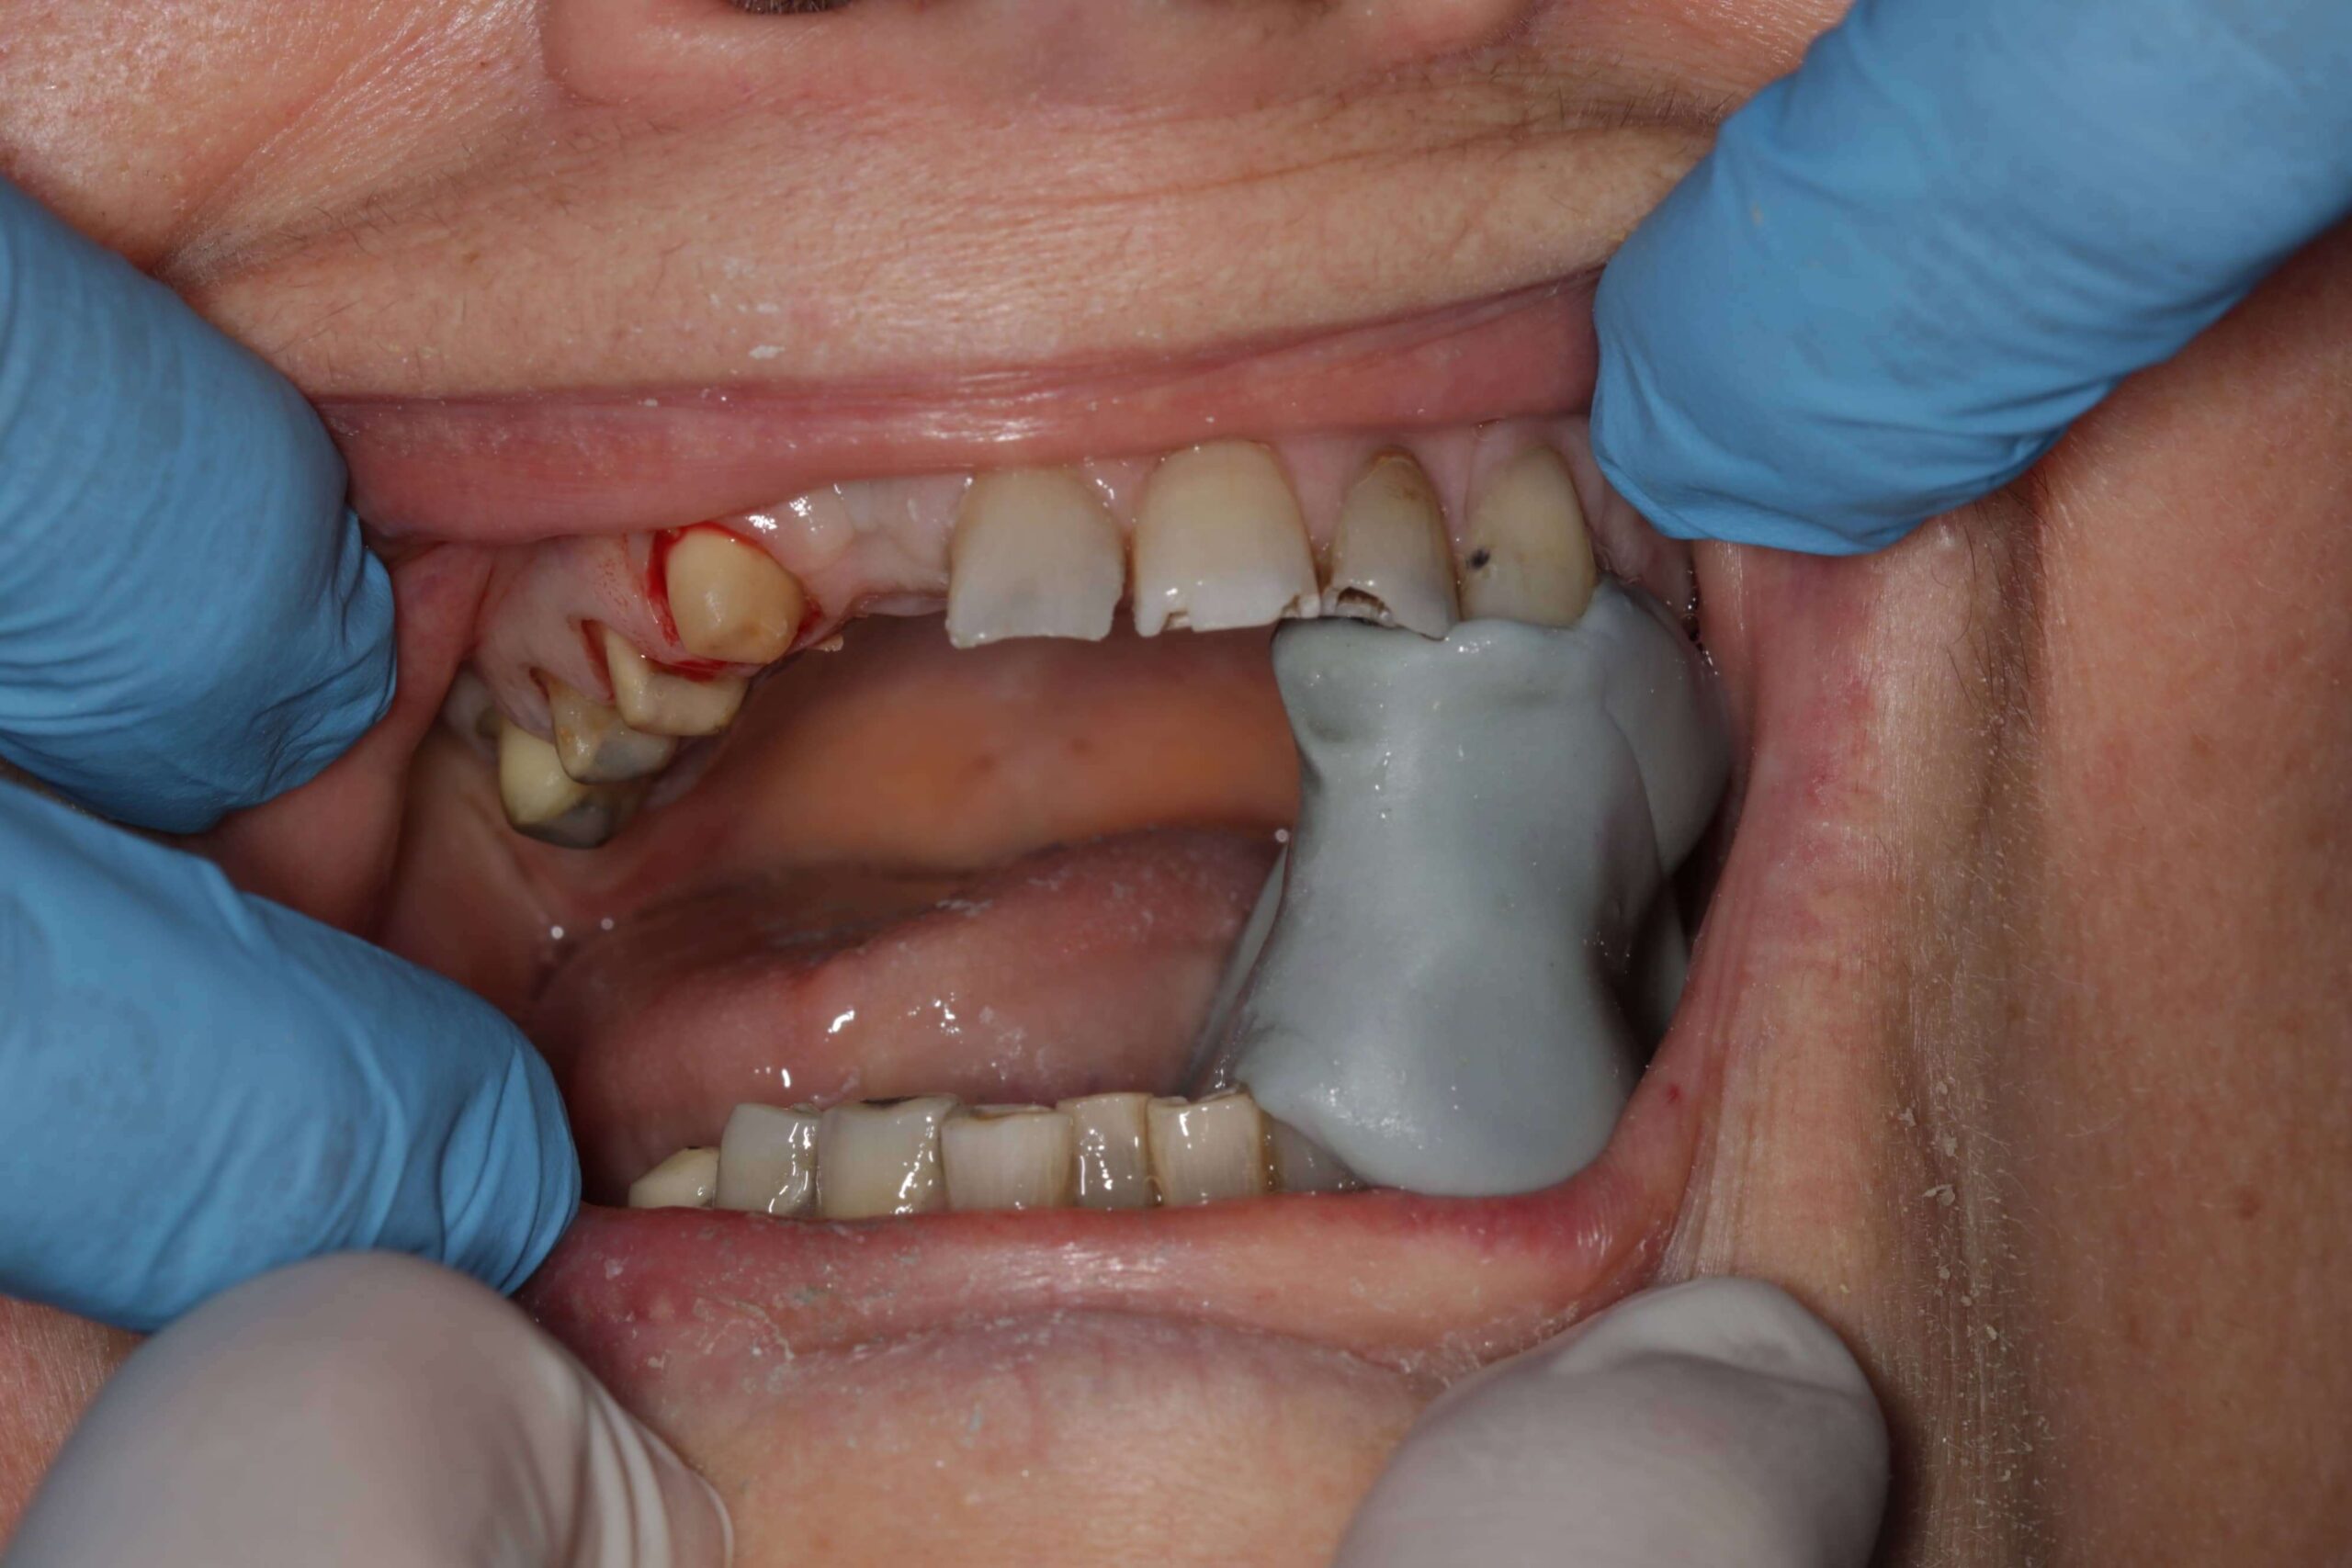

- Nem megfelelően kialakított fogpótlások: rosszul illeszkedő koronák, hidak vagy kivehető pótlások hosszú távon megváltoztathatják a harapási viszonyokat, túlterhelhetik az állkapocsízületet, és funkcionális egyensúlyzavart idézhetnek elő. Ez gyakran vezet feszüléshez, rágás közbeni fájdalomhoz vagy ízületi kattogáshoz.

Fogászati kezelés

- Fogtályog, szuvas fog, gyulladás vagy foghúzás utáni komplikáció esetén antibiotikumos kezelés, gyökérkezelés vagy sebészi beavatkozás lehet szükséges